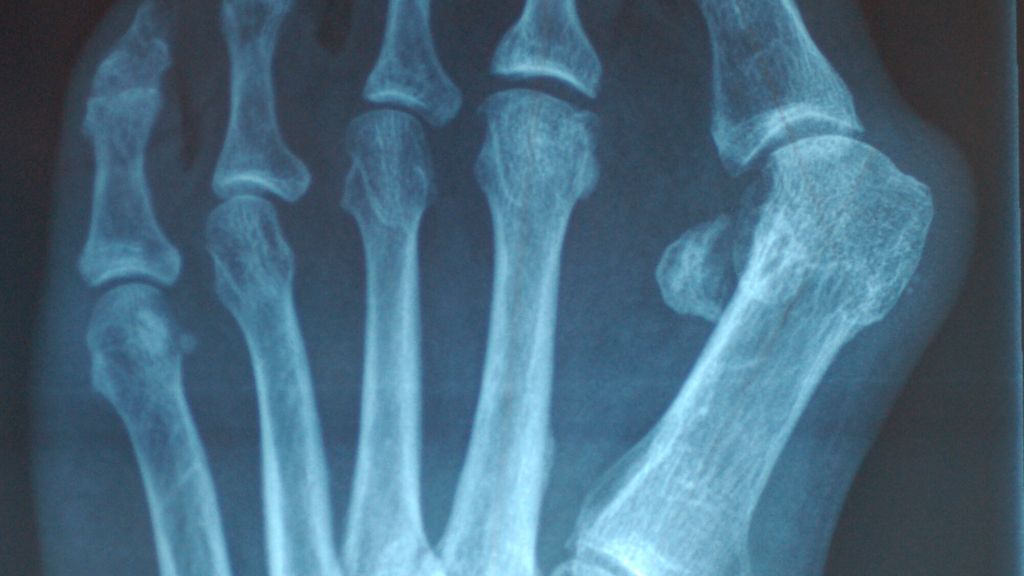

Abb. 2: Die übermäßige Pronation des M1 verstärkt die im Röntgen deutlich sichtbare Lateralisierung der Sesambeine

Die Rolle des M1 besteht in Hinblick auf den Großzeh darin, dass eine übermäßige M1-Pronation ein Ungleichgewicht auf die Strukturen des Metatarsophalangeal-1-Gelenks bringt, die medialen Bänder überdehnt werden und das M1-Köpfchen nach medial gleitet (Abb.1). Die Position der Sesambeinchen lateralisiert sich. Entweder sie bleiben in ihren Gelenksflächen, gehalten von den medialen und lateralen metatarsophalangealen Ligamenten – Kim et al. nennen das „Pseudoluxation“ – oder sie subluxieren aus ihren Metatarsalköpfchenführungen.15 Dies ist die häufigere Variante (Abb.2).